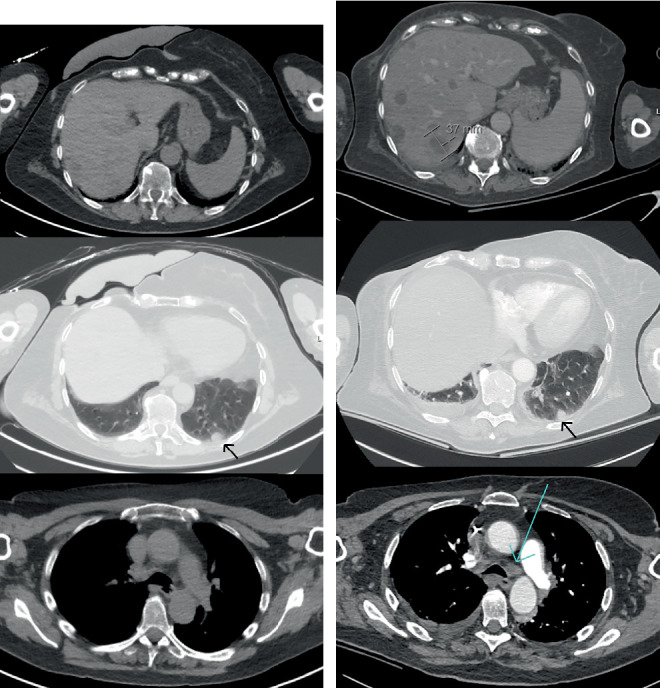

恶性肿瘤高钙血症是一种众所周知的癌症患者现象,往往与预后不良有关。免疫检查点抑制剂的发现通过改善许多不同癌症类型的预后,彻底改变了癌症治疗。不幸的是,免疫相关的不良事件经常发生,特别是双检查点抑制。我们提出一个病例严重高钙血症在一个65岁的妇女接受治疗转移性恶性黑色素瘤。在开始使用ipilimumab-nivolumab 11周后,患者出现严重的高钙血症,同时伴有炎症和肝炎。鉴于临床检查、影像学表现和实验室值可能与进行性疾病相一致,最初推测这是由于恶性肿瘤的高钙血症。高钙血症对双膦酸盐、静脉生理盐水和甲基强的松龙反应良好。有趣的是,出院后不久进行的氟脱氧葡萄糖-正电子发射断层扫描/计算机断层扫描(FDG-PET/CT)显示代谢完全缓解,因此不太可能出现恶性高钙血症。回顾病史、影像学和实验室检查,发现几个与结节样反应相符的特征。我们假设该反应导致1- α羟化酶升高,从而促进骨化三醇介导的高钙血症。在这篇报告中,我们总结了以前发表的关于免疫检查点抑制剂诱导的高钙血症的病例报告,并讨论了在这种罕见的免疫相关不良事件中引起高钙血症的各种机制。免疫检查点抑制剂可以诱导甲状旁腺激素相关蛋白(PTHrP)、骨化三醇的产生,并可能导致低皮质醇血症,所有这些都可以破坏钙稳态。通过这个病例,我们提供了越来越多的证据,证明高钙血症是一种免疫相关的不良事件,并旨在提高临床医生对这种潜在并发症的认识。早期识别对这种危及生命的疾病至关重要,因为它对常规治疗是难治性的,可能需要皮质类固醇治疗。

Hypercalcemia of malignancy is a well-known phenomenon in cancer patients, often associated with poor prognosis. The discovery of immune checkpoint inhibitors has revolutionised cancer therapy by improving prognosis in numerous different cancer types. Unfortunately, immune-related adverse events frequently arise, particularly with dual checkpoint inhibition. We present a case of severe hypercalcemia in a 65-year-old woman undergoing treatment for metastasised malignant melanoma. Eleven weeks after initiating ipilimumab-nivolumab, the patient developed severe hypercalcemia, along with inflammation and hepatitis. This was initially presumed to be due to hypercalcemia of malignancy, given the clinical examination, imaging findings and laboratory values potentially consistent with progressive disease. The hypercalcemia responded well to bisphosphonates, intravenous saline and methylprednisolone. Interestingly, fluorodeoxyglucose-positron emission tomography/computed tomography (FDG-PET/CT) performed shortly after hospital discharge showed a complete metabolic remission, thereby making hypercalcemia of malignancy unlikely. Review of her medical history, imaging and laboratory revealed several features consistent with a sarcoid-like reaction. We hypothesise that this reaction led to elevated 1-alpha hydroxylase, thereby facilitating calcitriol-mediated hypercalcemia. In this report, we summarise previously published case reports on immune checkpoint inhibitor-induced hypercalcemia and discuss the various mechanisms that cause hypercalcemia in this rare immune-related adverse event. Immune checkpoint inhibitors can induce production of parathyroid hormone-related protein (PTHrP), calcitriol, and may cause hypocortisolaemia, all of which can disrupt calcium homeostasis. Through this case, we contribute to the growing body of evidence regarding hypercalcemia as an immune-related adverse event and aim to raise awareness among clinicians of this potential complication. Early recognition is critical for this life-threatening condition, as it can be refractory to conventional therapies and may necessitate corticosteroid therapy.